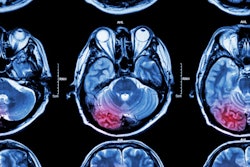

With color coding versus without, "there's a lot more information visible in the scan" showing asymmetry in perfusion between the left and right in an acute stroke patient, Meijs said of one example.

In the 3D volume rendering above, the reader can see a patient-specific color map, indicating the arrival time of blood to the brain. The color difference between the left and right hemisphere is caused by a vascular occlusion in the M1 segment. Due to collateral flow, the affected hemisphere is supplied with blood at a later arrival time, with orange and red hues indicating contrast arrival times several seconds later than green and blue. The green image below lacks color coding and took longer to interpret. Images courtesy of Midas Meijs.Overall, the average time to detection decreased from 37 seconds to 19.4 seconds (p < 0.03), and the average accuracy of vessel occlusion detection increased insignificantly from 0.825 to 0.85 with the use of color mapping. A single false-positive vessel occlusion was called by both observers using color mapping. However, both observers found the technique helpful and time-saving.